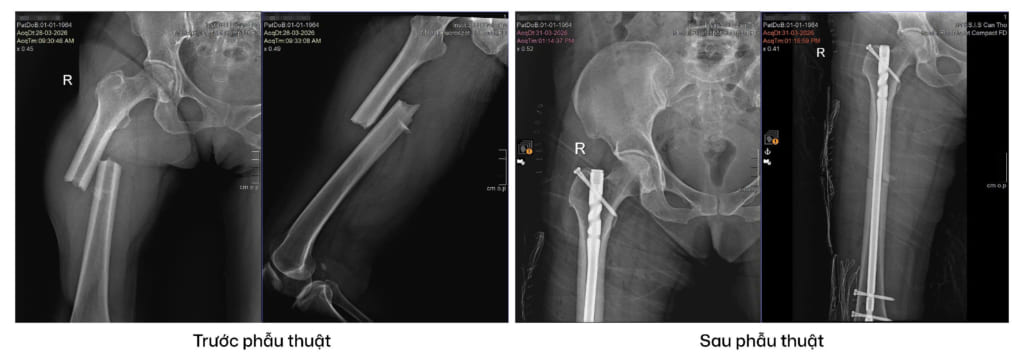

Trường hợp này, bệnh nhân có tiền sử bệnh tim mạch, tăng huyết áp và đái tháo đường nên đã được hội chẩn liên chuyên khoa trước khi quyết định phẫu thuật. Phương pháp được lựa chọn là kết hợp xương bằng đinh nội tủy xương đùi, một kỹ thuật hiện đại trong chấn thương chỉnh hình giúp cố định ổ gãy vững chắc và tạo điều kiện cho bệnh nhân sớm vận động.

Ca phẫu thuật diễn ra thuận lợi trong khoảng 35 phút. Sau mổ, bệnh nhân hồi phục tốt, vết mổ ổn định, có thể ăn uống, vận động nhẹ sau 24 giờ và tập đi với khung hỗ trợ trong những ngày tiếp theo. Bệnh nhân được xuất viện sau 3 ngày điều trị.